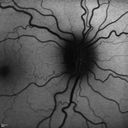

Acute Posterior Multifocal Placoid Pigment Epitheliopathy - APMPPE - SD-OCT 1310 views 25-year-old man with one and half weeks ago he woke up with night chills. Also around that time his joints started hurting him. He also has headaches, although the headache at this point is not severe. His vision has been changing for about the last week and a half. He sees some spots in his vision and they are blurred spots. They are not in the central vision.

VISUAL ACUITY: OD 20/32, OS 20/32

Acute Posterior Multifocal Placoid Pigment Epitheliopathy - APMPPE - SD-OCT 1275 views 25-year-old man with one and half weeks ago he woke up with night chills. Also around that time his joints started hurting him. He also has headaches, although the headache at this point is not severe. His vision has been changing for about the last week and a half. He sees some spots in his vision and they are blurred spots. They are not in the central vision.